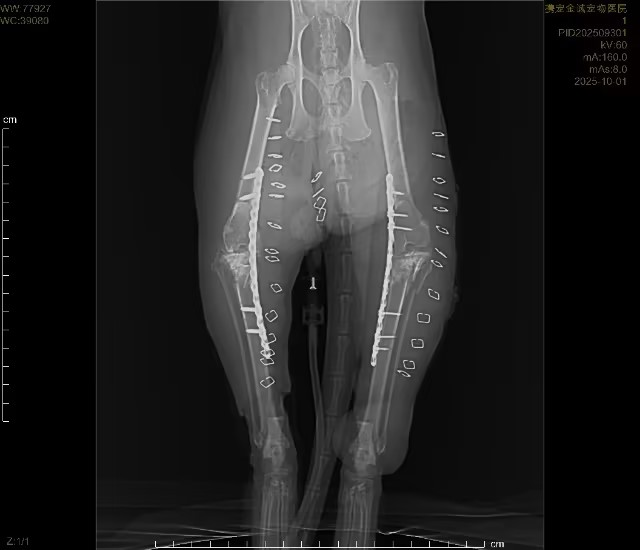

四、核心诊疗亮点:联合浙江大学教授·骨02胶水微创骨骼修复手术

针对猫咪高空坠落导致的骨骼创伤,我院启动重症创伤多学科联合救治,突破传统手术局限:

- 专家联合主刀:特邀浙江大学权威骨科教授亲临我院,全程指导并参与手术,保障手术安全性与精准度

- 创新技术应用:采用骨02胶水进行骨骼微创固定手术并结合传统钢板、钢钉固定

手术优势:

- 创口极小,对坠楼后虚弱机体损伤更低

- 骨骼固定牢固,稳定性强

- 术后愈合快,大幅缩短康复周期

- 减少感染、出血、二次损伤等并发症

- 联合救治:手术同期开展保肝、护肾、纠正凝血、控制炎症、纠正代谢紊乱等综合重症支持治疗,实现“骨骼修复+内脏保护”双保障。